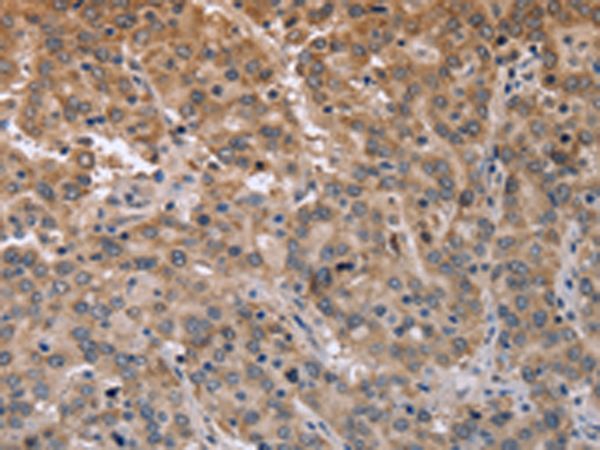

分类: 科研抗体货号: P08272别名: EIF-4B; PRO1843应用: IHC反应种属: Human, Mouse